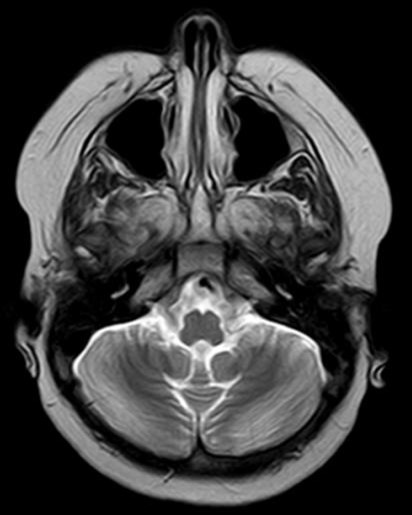

¿Cómo interpreta las imágenes de RM craneal?: